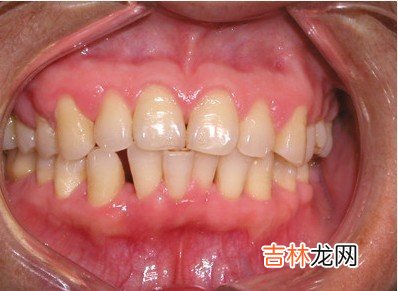

【单纯性牙周炎的治疗原则是什么】 治疗成人牙周炎强调早期诊断,早期治疗 。治疗应坚持以局部治疗为主、全身治疗为辅的原则 。大多数患者经过恰当治疗后,病情可得到控制 。

局部治疗包括以下几个方面:控制菌斑,彻底清除牙石,平整根面;牙周袋及根面的药物处理;牙周手术;固定松动牙;拔除不能保留的患牙,以利于邻牙的治疗和组织恢复 。菌斑是牙周病的主要病原刺激物,刷牙是清除菌斑的主要手段,但患者必须选用设计科学的牙刷,掌握正确的刷牙方法,才能有效地去除菌斑 。牙石是矿化了的菌斑,清除龈上牙石称为洁治术,龈下牙石的清除称为龈下刮治术,洁治和刮治术是牙周病的基础治疗,任何其他治疗手段只应作为基础治疗的补充手段 。对一些炎症严重、有肉芽增生的深牙周袋,在刮治术后需用药物处理袋壁 。可在牙周袋内放置抗菌药物,如甲硝唑、四环素、洗必泰等,采用缓释剂型,疗效更好 。经过上述治疗后,若仍有深牙周袋存在,或根面牙石不易清除彻底,可进行牙周手术 。松动牙固定术是用金属丝将患牙与邻近的稳固牙齿结扎在一起,并以自凝塑胶加固(制成牙周夹板),使牙合力分散于一组牙上,减少个别牙的负担或使其免受侧向扭转力的损害,以利于牙周组织的修复 。单纯性牙周炎一般为慢性过程,除非出现急性症状,一般不采用抗生素类药进行全身治疗 。对严重病例可口服甲硝唑或螺旋霉素等,使急性炎症得到控制 。有些病员有慢性系统病如糖尿病、贫血、消化道疾病等,这些全身疾病可能与牙周炎互相影响,加速牙周组织的破坏,因此须同时控制全身疾病 。